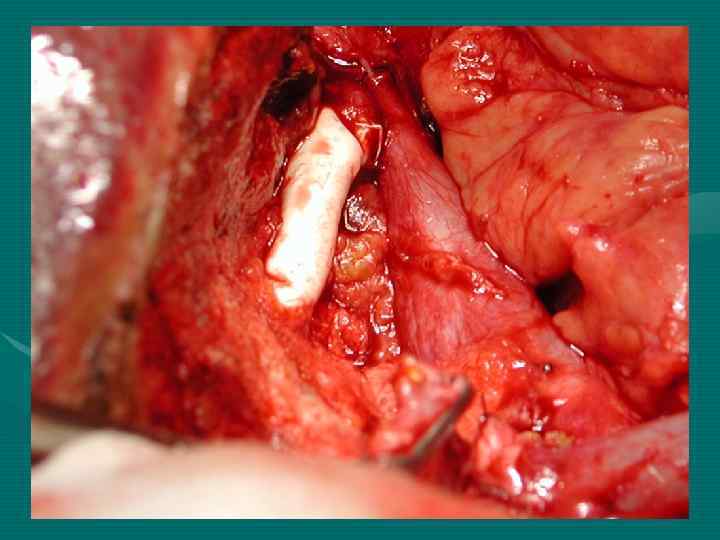

Стандартные показания Современный подход Нет инвазии НПВ и устья печеночных вен. Нет ограничений. Резекция НПВ или печеночных вен с реконструкцией.